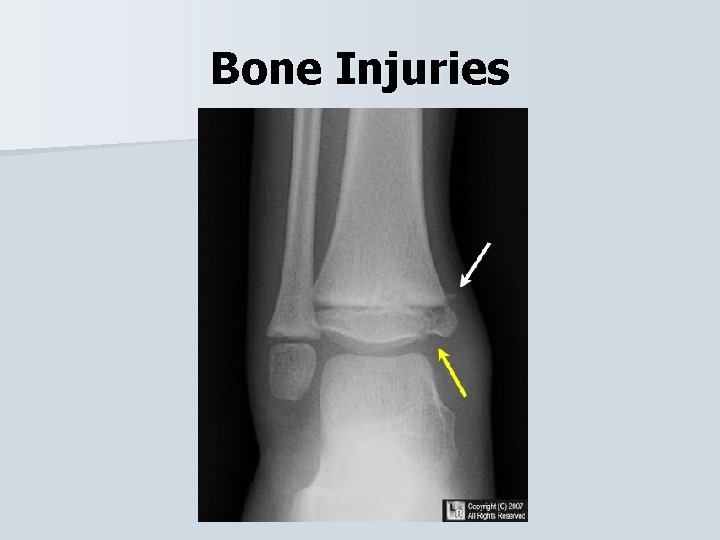

Bone Injuries Epiphyseal Fx • Distal tibia and fibula fracture of the epiphysis, or growth plates can become injured when the ankle is forced into plantar flexion and eversion. • The athlete will experience pain & swelling over the epiphysis and difficulty walking/running. • Splint the injury and refer to physician.

Bone Injuries